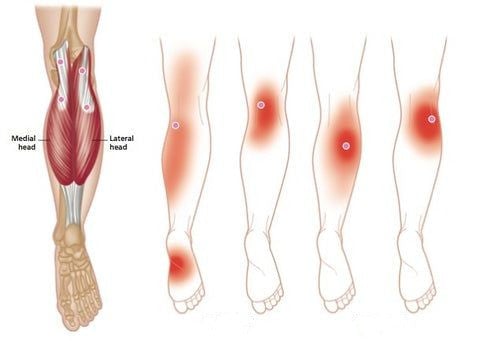

האם ניתן להשתמש בברך כל היום?

כן, בזכות הבד הנושם שלה, היא נוחה ללבישה כל היום ללא אי נוחות.

האם היא מתאימה לפעילויות ספורטיביות?

כן, היא מספקת תמיכה מצוינת לפעילויות מתונות, תוך הפחתת הסיכון לפציעות.

לא, החום נוצר באופן טבעי על ידי חלקיקי טורמלין במגע עם עורכם.